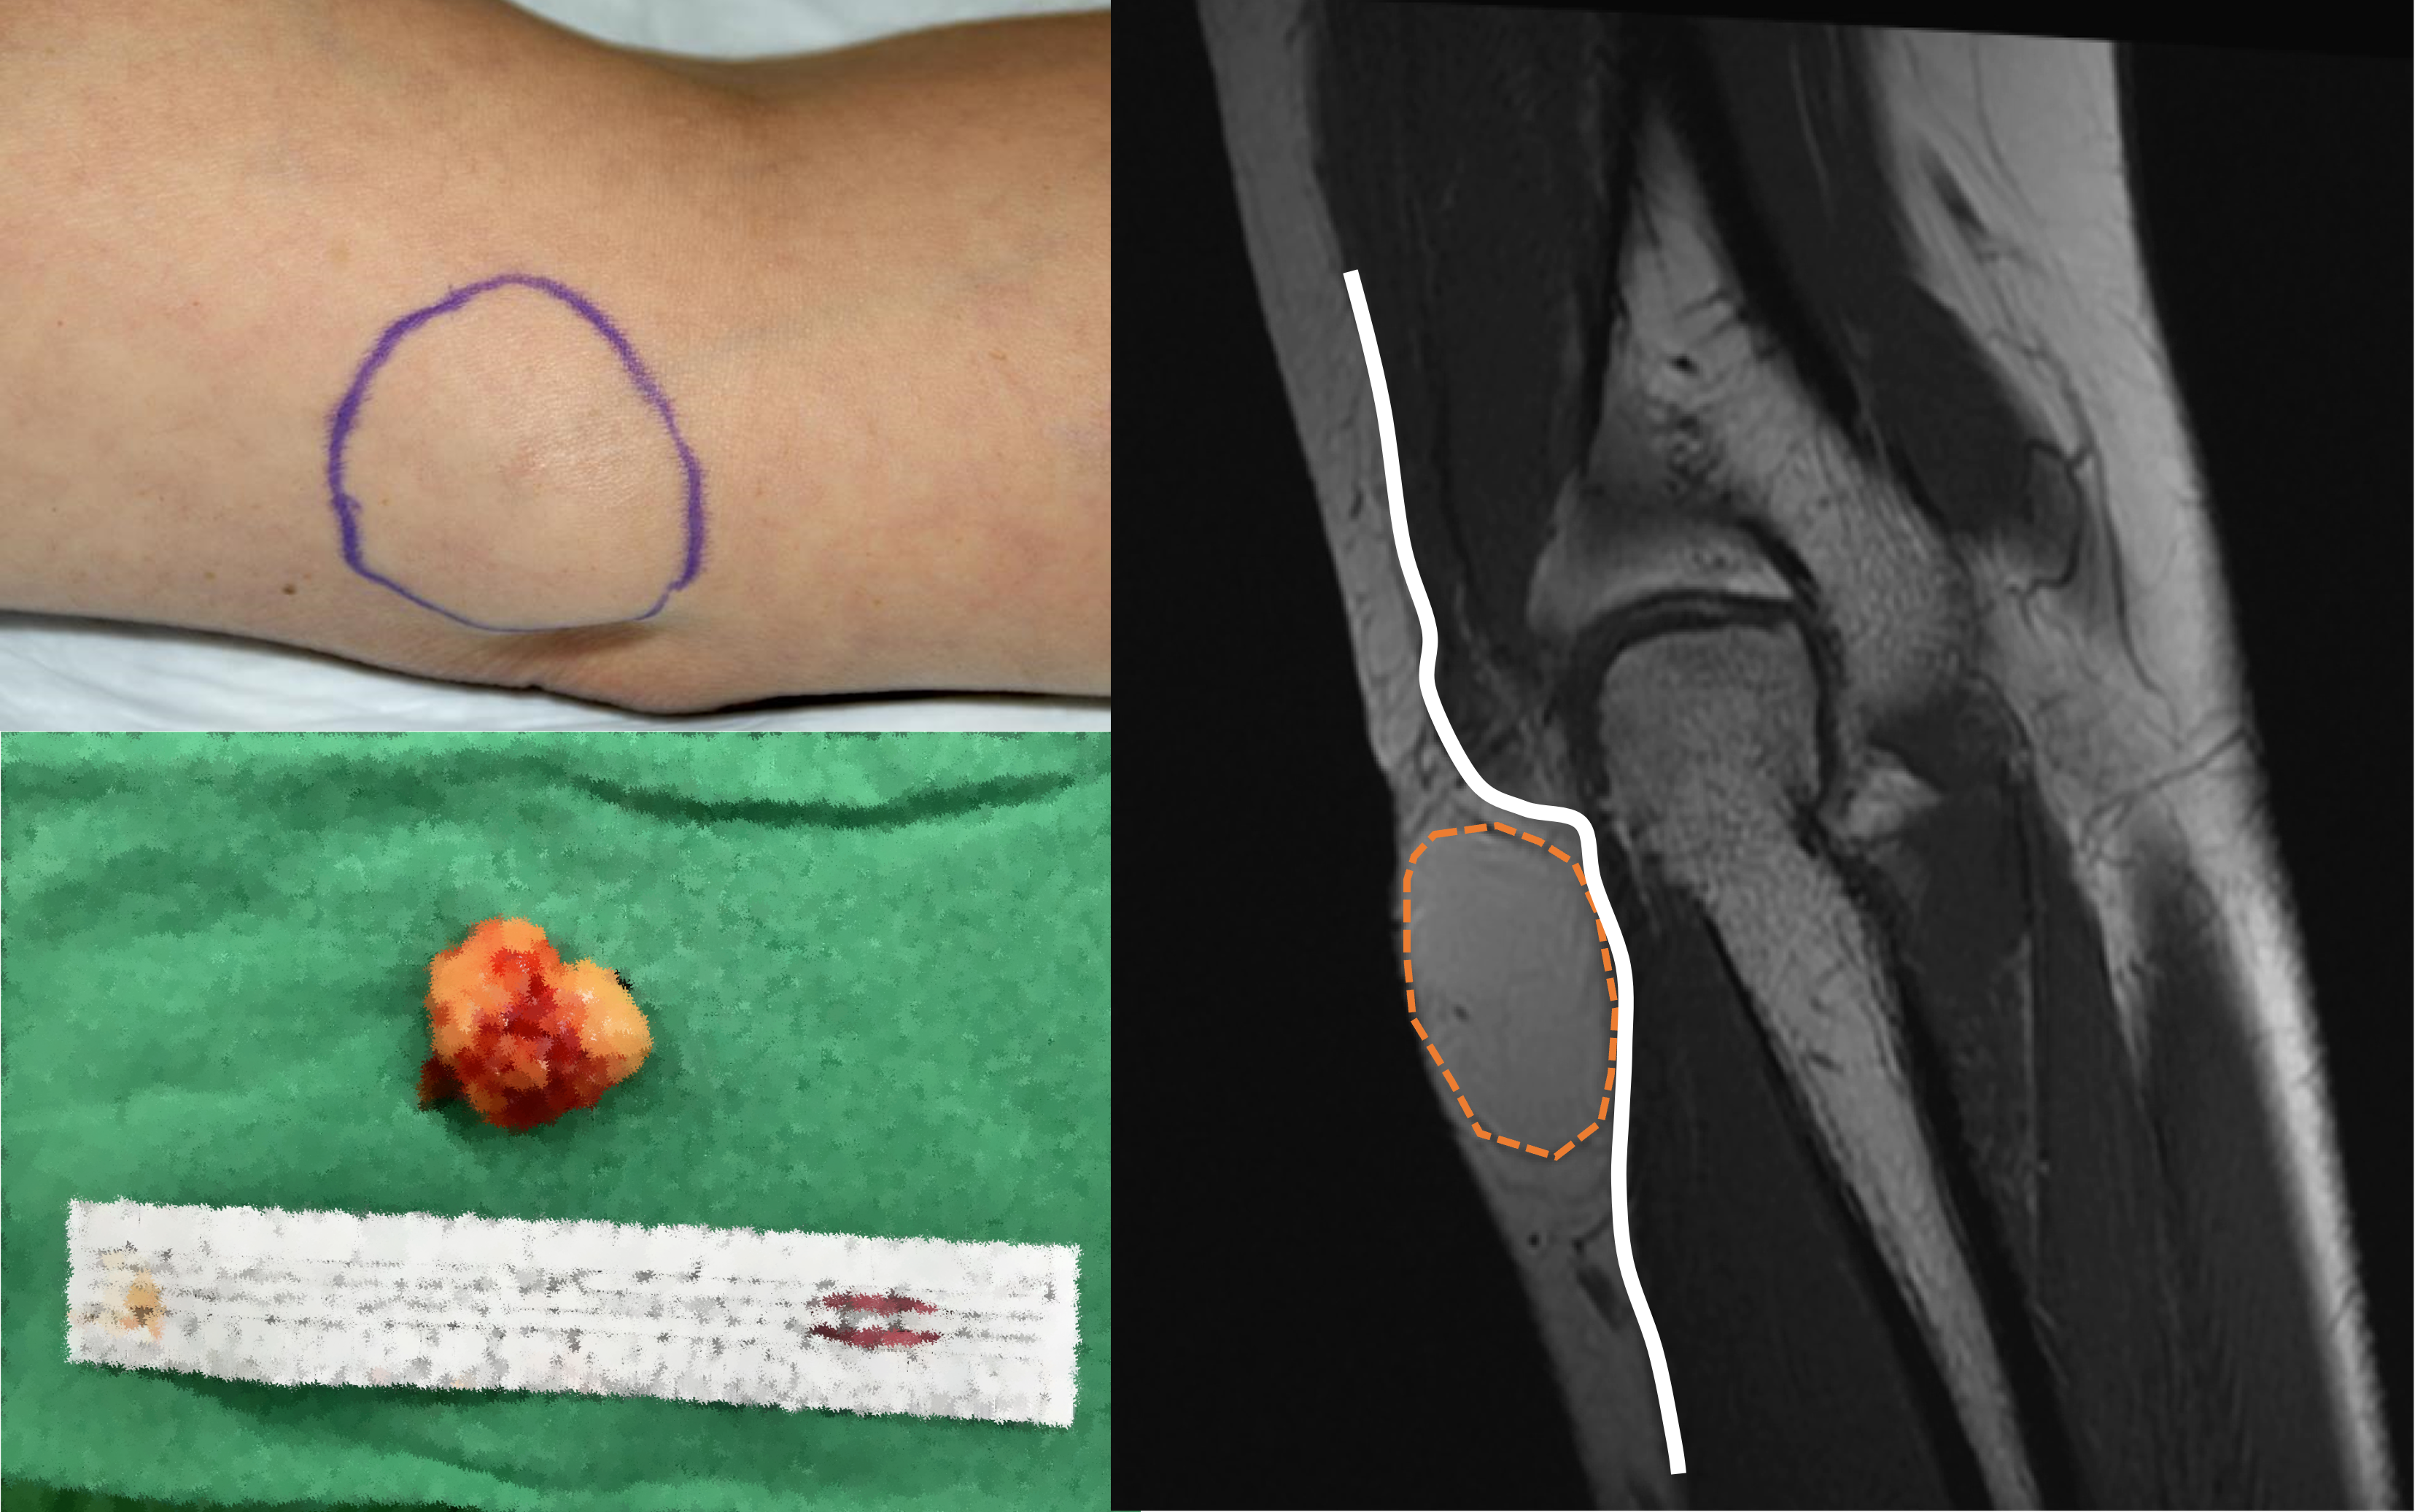

上圖左上為脂肪瘤外觀,看起來並不明顯,圖右看到腫瘤位置(橘圈)位在筋膜(白線)之上,因此診斷為良性脂肪瘤,因有神經壓迫症狀,故進行手術切除(圖左下)